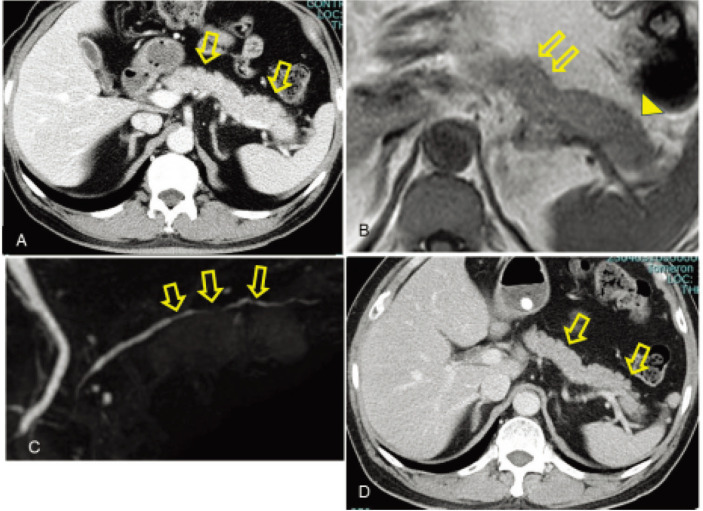

Diet-related cardiometabolic diseases and inflammatory bowel disease, common previously in Western countries, are global problems. We hypothesized that inflammatory bowel disease is a lifestyle disease primarily mediated by the current Western diet. We report here the simultaneous onset of ulcerative colitis and autoimmune pancreatitis, a rare systemic complication of inflammatory bowel disease, 2 months after acute myocardial infarction in a patient with type 2 diabetes. A 67-year-old man with type 2 diabetes was referred to us because of newly diagnosed ulcerative colitis 2 months after acute myocardial infarction. A plant-based diet was provided during hospitalization. An abrupt deterioration in plasma glucose and hemoglobin A1c due to asymptomatic type 2 autoimmune pancreatitis was observed. Prednisolone administration under intensive insulin therapy led to the remission of both diseases. This case was an illustrative one of association between cardiometabolic diseases and inflammatory bowel diseases caused by current unhealthy diets and their shared pathogenesis.